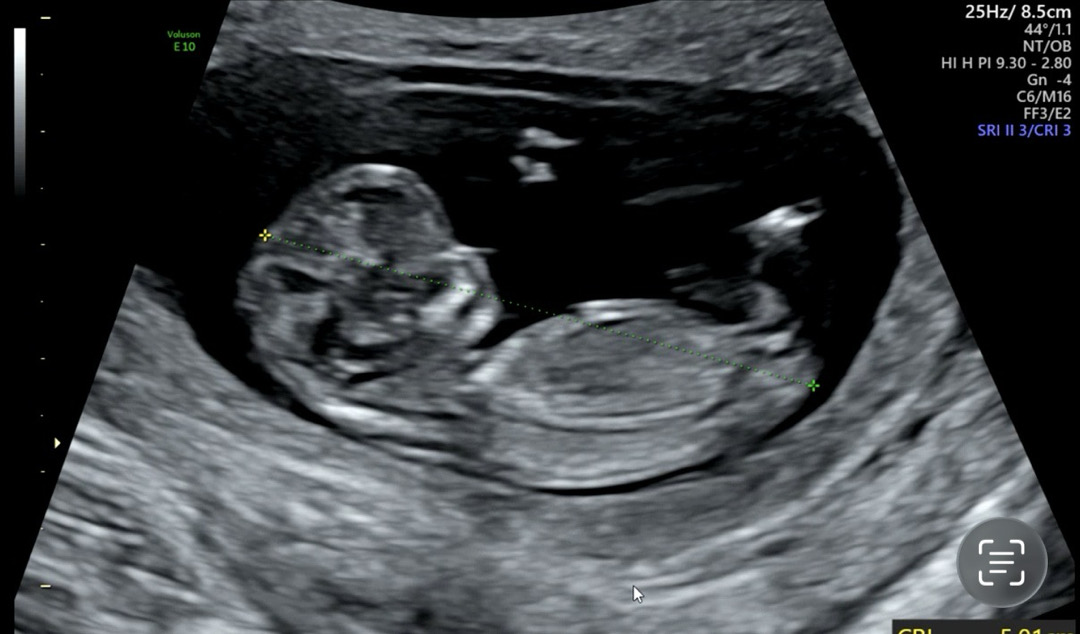

아들일까요? 딸일까요?

11주차 3일입니다~ 어떻게 보이세요?